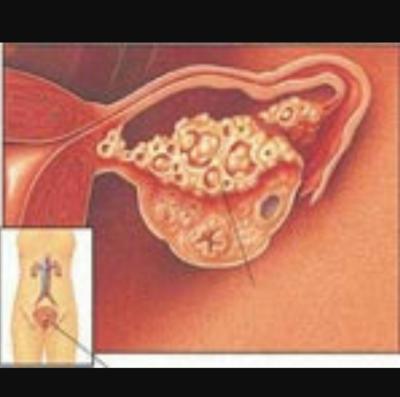

Kisti olup hamile kalanlar kist hamile kalmaya engelmidir kist varken hamile kalınırmı kist hamile kalmamda sorun yaratırmı kist ve gebelik hakkında bilgiler bazı kadınlar kistleri oldugu için bazen hamile kalmayabilir ancak 3 cm lik kisti olupta hamile kalan birsürü insan var. şubatta kontrole gideceğim umarım ben de hamile kalabilirim hayırlısıyla. Adet sancıları şiddetli olan derin cinsel ilişkide ağrısı olan karında ve kasıkta ağrıları bulunan kanlı dışkılama idrarda yanma ve kanama olması adet kanaması olduğunda burun kanaması olan vücudunda değişik yerlerde morluklar oluşan ve üreme çağında olan kadınların çikolata kisti açısından tehdit altında. çikolata kisti hamile kalmayı nasıl engeller.

Kisti olup hamile kalanlar. çikolata kisti olup sol tüpü kapalı hamile kalanlar çikolata kisti. Bunun opere olması şart değil. şubatta kontrolüm var dua ediyorum o zamana kadar hamile kalayım diye teşekkür ederim geçmiş olsun size de dermoid kistler ilaçla küçülmüyor maalesef benim de ilk dr görmemişti kisti alttan ultrasonla bakmasına rağmen 2.

Kizlar ankarada 2 devlet kadindogum hastanesi gezdim ama beni mahvettiler. çikolata kisti olup sol tüpü kapalı hamile kalanlar çikolata kisti. Merhaba kistler türüne göre gebe kalmada sıkıntı yaratır çikolata kisti de hamile kalmaya engel olan kistler den biri. Kistimin polikist oldugunu adet gorunce gectigini soylediler ve suan 2 yillik evliyim ozel hastane adini cok duydugum hulisi bulent zeynelogluna gittim dermoid kistimin oldugunu soyledi ameliyat oldum bugun 3.